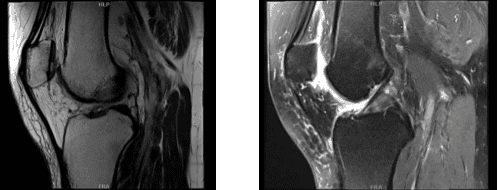

We agreed to go with 3 tesla MRI of Right knee, the results were reviewed and discussed by the doctor, there is no acute fracture or osteonecrosis. The Ligaments, cruciate and collateral ligaments are intact, the Lateral compartment meniscus demonstrates a partially discoid configuration.

There is a partial superior articular surface tear within the anterior horn of the lateral meniscus (sagittal image 14). No full-thickness cartilage defect is seen, there is tiny marginal osteophytosis.

Medial compartment is intrasubstance degenerative signal within the body and posterior horn of the medial meniscus without extension to an articular surface to constitute tear.

Mild free edge margin fraying is noted. There is mild to moderate thinning of the central weight bearing cartilage with focal full-thickness delamination at the medial femoral condyle where there is mild marginal edema.

The Patellofemoral compartment is moderate thinning overlying the central and medial trochlear cartilage with an 8 mm near full-thickness cartilage defects. There is an additional full thickness cartilage fissuring at the median ridge of the patella spanning 3 x 6 mm with a nondisplaced cartilage flap.

Muscle/tendon, the periarticular muscles are maintained. The imaged tendons, inclusive of the extensor mechanism, are intact. Joint fluid: There is a small-moderate joint effusion. No popliteal cyst is seen. There are no intra-articular ossific loose bodies. Mild anterior subcutaneous edema is noted.

The neurovascular structures demonstrate normal course. Partial anterior lateral meniscus tear. Moderate medial compartment cartilage wear. Tricompartmental cartilage wear with full-thickness loss most notably at the patellofemoral compartment where there is a 6 mm nondisplaced patellar cartilage flap.

MRI-3T Right knee non-contrast